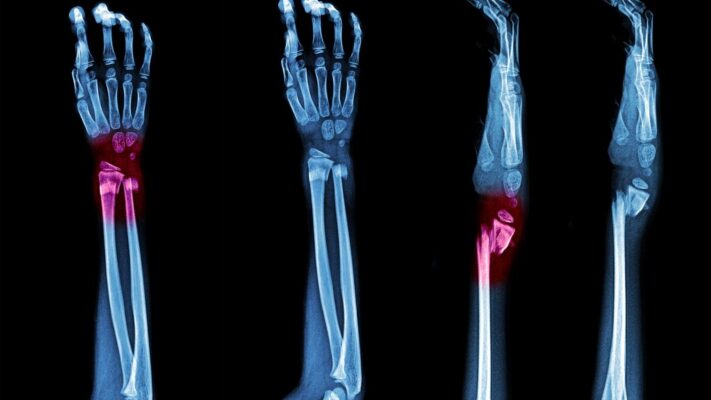

- Stres kırıkları

Özellikle stres kırıkları, yoğun aktivite yapan bireylerde sıkça görülür ve ağrısı nöromayı taklit edebilir. Bursit dediğimiz sıvı dolu keseciklerin iltihaplanması da sinire baskı yaparak benzer şikayetlere yol açabilir. Bu nedenle sadece şikayetlere dayalı değil kapsamlı bir değerlendirme ile tanı koymak esastır.